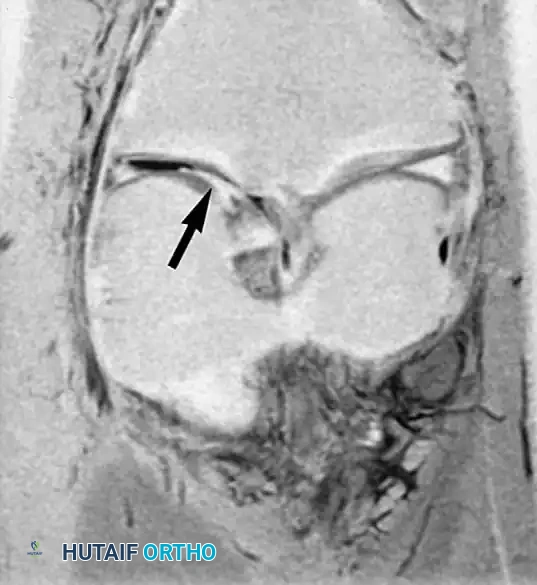

التمزقات المعقدة والمزاحة

بعض التمزقات تكون شديدة لدرجة أن جزءا من الغضروف ينفصل وينزاح من مكانه الأصلي ليستقر في منتصف المفصل، مثل تمزق يد الدلو، مما يسبب انغلاق الركبة الميكانيكي.

في حالات أخرى، قد ينزاح الجزء الممزق إلى الأسفل تحت الأربطة الجانبية.